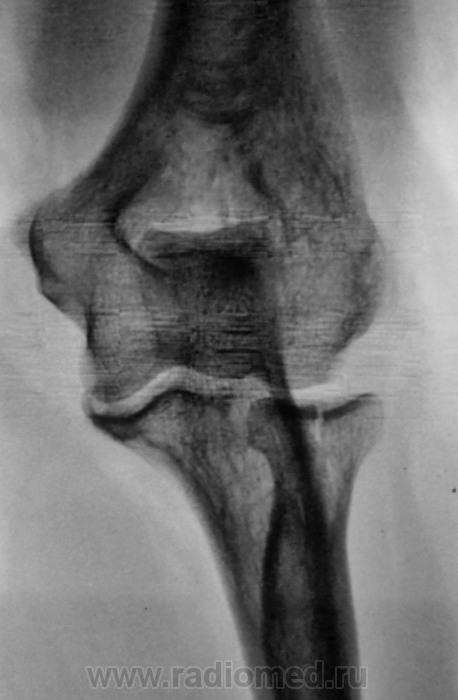

Пол пациента: Женский пол Тип патологии: Травма Область исследования: Скелетно-мышечная система Методы исследования: Rg Просто так..., но травма была. https://radiomed.ru/sites/default/files/styles/case_slider_image/public/user/12/2.201402220009.jpg?itok=LGvPgd58 ID:35743 Mon, 24/02/2014 - 15:21 #1 Сергей Кузьминов Offline Last seen: 1 year 1 month ago Joined: 06.10.2012 - 15:51 Posts: 11813 Внутрисуставной перелом головки лучевой кости.Бывает. Mon, 24/02/2014 - 20:21 #2 И.Бондаренко Offline Last seen: 3 days 16 hours ago Joined: 13.09.2011 - 22:55 Posts: 9208 +1 Mon, 24/02/2014 - 22:57 #3 алкс Offline Last seen: 10 years 2 months ago Joined: 24.10.2012 - 22:55 Posts: 2915 Сергей Кузьминов wrote: Внутрисуставной перелом головки лучевой кости.Бывает. Вообще-то не все так просто. Обычно гемартроз бывает. Кстати - где боковой? Tue, 25/02/2014 - 08:47 #4 Катенёв Валенти... Offline Last seen: 7 years 2 months ago Joined: 22.03.2008 - 22:15 Posts: 54876 алкс wrote: Сергей Кузьминов wrote: Внутрисуставной перелом головки лучевой кости.Бывает. Вообще-то не все так просто. Обычно гемартроз бывает. Кстати - где боковой? Боковой есть (стандарт блюдём). Решил боковой не вставлять так как перелома на нем не видно, вот и ветка названа так - "просто так"...

Внутрисуставной перелом головки лучевой кости.Бывает.

Вообще-то не все так просто. Обычно гемартроз бывает. Кстати - где боковой?

Боковой есть (стандарт блюдём). Решил боковой не вставлять так как перелома на нем не видно, вот и ветка названа так - "просто так"...